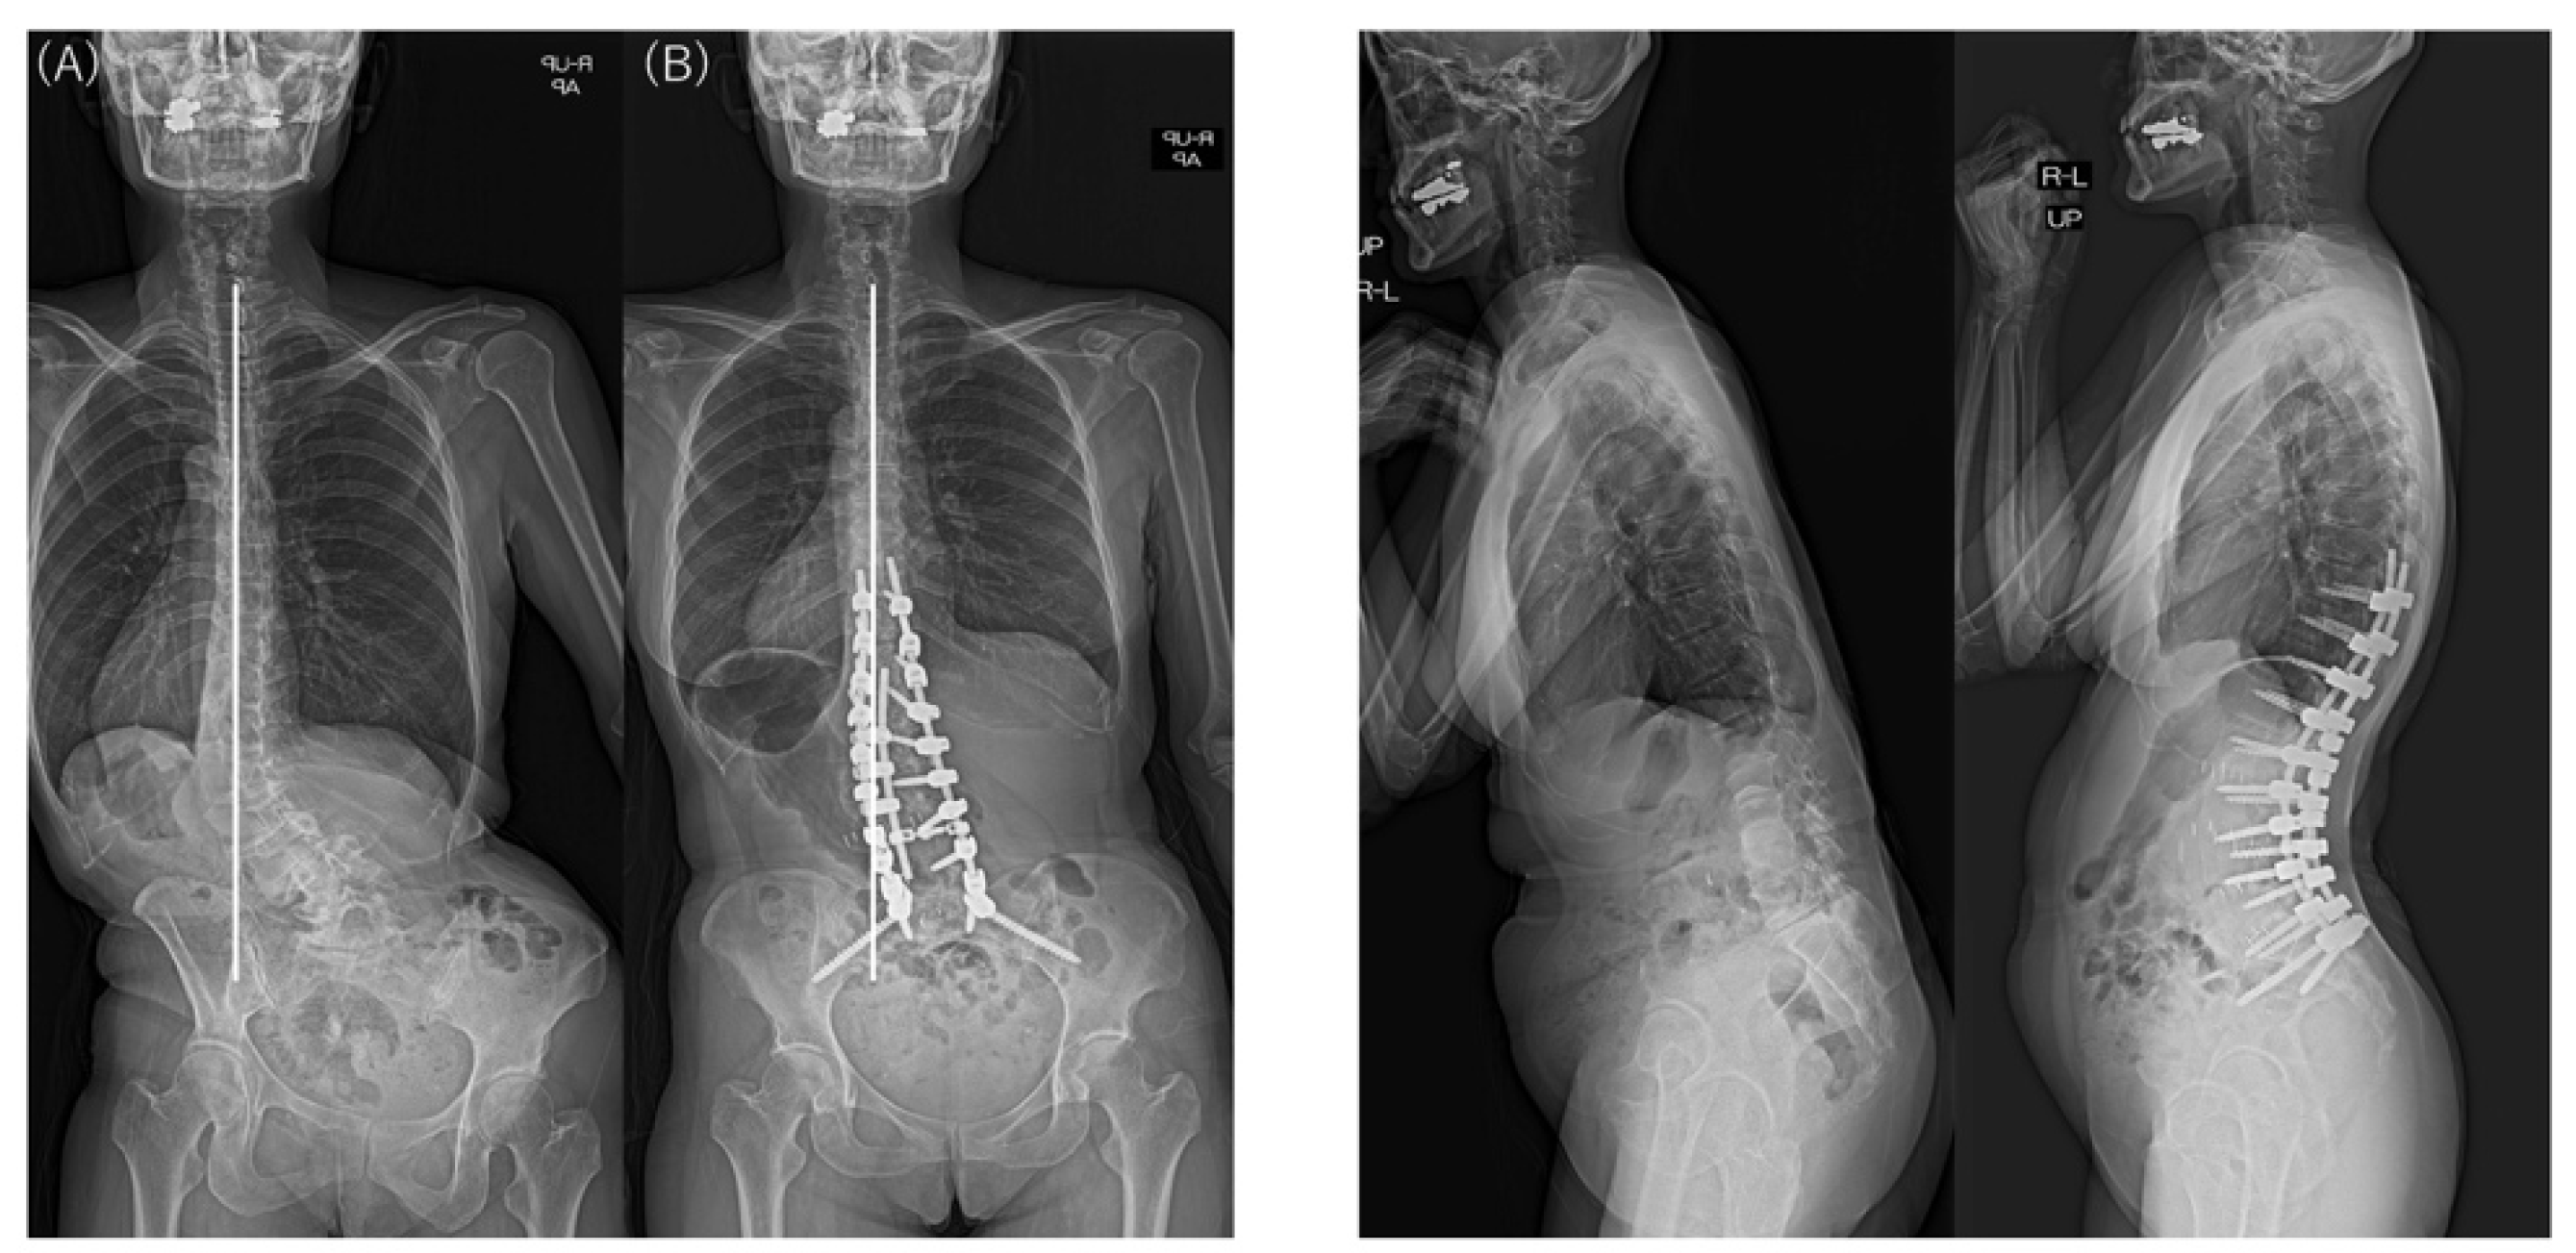

| Major Cobb angle (°) | Preop | 50.0 (11.4) | 44.3 (11.4) | 48.8 (11.5) | 0.286 |

| Last | 12.9 (11.9) | 14.2 (8.0) | 13.2 (11.1) | 0.810 | |

| p † | <0.001 * | 0.002 * | <0.001 * | ||

| │CBD│ (mm) | Preop | 78.4 (51.6) | 46.9 (21.7) | 71.9 (48.5) | 0.159 |

| Last | 22.8 (28.0) | 38.5 (20.4) | 26.0 (27.0) | 0.211 | |

| p † | <0.001 * | 0.506 | <0.001 * | ||

| SVA (mm) | Preop | 168.0 (75.9) | 172.9 (35.1) | 169.0 (69.0) | 0.879 |

| Last | 36.3 (56.3) | 53.3 (39.9) | 36.9 (53.4) | 0.494 | |

| p † | <0.001 * | 0.001 * | <0.001 * | ||

| Type 1A | 23 | 16 | 7 | 69.6% |

| Type 2A | 6 | 1 | 5 | 16.7% |